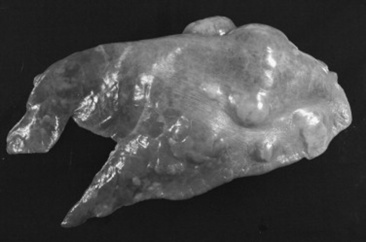

The upper airway can be directly examined with the aid of an endoscope, the only limitations being the size of the patient, the patency of the airway, and the size of the available equipment. Standard flexible fiberoptic endoscopes, available to most practitioners and present now in virtually all referral hospitals, allow direct examination of the nasal passages, ethmoid turbinates, nasal maxillary opening of the sinuses, pharynx, guttural pouch openings, larynx, and cranial trachea (Fig. 31-1). Smaller (8- to 10-mm-diameter) endoscopes can be readily introduced into the equine guttural pouches with the aid of a biopsy instrument, and longer endoscopes (more than 150 cm long with diameters greater than 10 mm) are commonly employed to examine mainstem bronchi and their initial branches in large animals.3 Small brushes, used for collecting exfoliated cells for cytologic study, and a variety of biopsy instruments can be used for sampling the airway. The use of airway endoscopy has evolved to include videoendoscopy of the equine upper airway during treadmill exercise at high speed (12 to 14 m/sec) to evaluate dynamic respiratory function and make objective measurements by use of freeze-frame features.4

Fig. 31-1 Normal equine larynx. The larynx is directly visualized by endoscopy, with both structure and symmetry evaluated.

Courtesy Dr. Corinne Sweeney, University of Pennsylvania, New Bolton Center, Kennett Square, Penn.